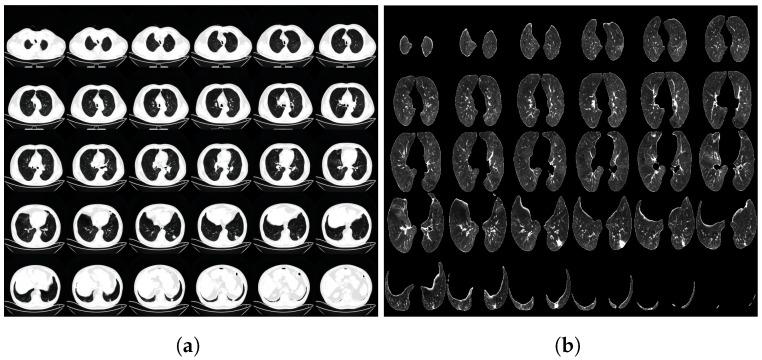

As the number of modalities in biomedical data continues to increase, the significance of multi-modal data becomes evident in capturing complex relationships between biological processes, thereby complementing disease classification. However, the current multi-modal fusion methods for biomedical data require more effective exploitation of intra- and inter-modal interactions, and the application of powerful fusion methods to biomedical data is relatively rare. In this paper, we propose a novel multi-modal data fusion method that addresses these limitations. Our proposed method utilizes a graph neural network and a 3D convolutional network to identify intra-modal relationships. By doing so, we can extract meaningful features from each modality, preserving crucial information. To fuse information from different modalities, we employ the Low-rank Multi-modal Fusion method, which effectively integrates multiple modalities while reducing noise and redundancy. Additionally, our method incorporates the Cross-modal Transformer to automatically learn relationships between different modalities, facilitating enhanced information exchange and representation. We validate the effectiveness of our proposed method using lung CT imaging data and physiological and biochemical data obtained from patients diagnosed with Chronic Obstructive Pulmonary Disease (COPD). Our method demonstrates superior performance compared to various fusion methods and their variants in terms of disease classification accuracy.